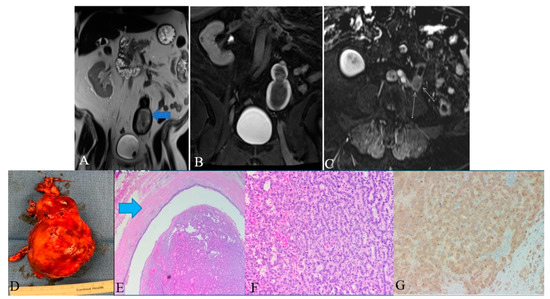

Figure 13. A 48-year-old female with ureteral NENs. (A) Coronal T2 nonfat sat image shows a large expansible hematoma in the ureteric stump (arrows). (B) Coronal T1 postcontrast delayed fat sat image: Shows a large expansible hematoma with intrinsic high T1 signal. (C) Axial T1 postcontrast delayed fat sat subtraction image: a small enhancing nodule (arrows) along the superior aspect of the stump. (D) Left lower ureter mass consists of a segment of the ureter with an attached firm, tan-brown, irregular, mass, measuring 11.5 × 7.0 × 6.0 cm. (E) E&H staining: 20× shows polypoid tumor bulging into the ureter lumen. Normal urothelial mucosa and muscle layer can be seen on the top half (arrow). (F) H&E straining: 200× high-power view shows tumor cells arranged in a trabecular and tubular pattern. (G) Synaptophysin staining: 200× shows tumor cells expressing synaptophysin (brown staining), which is a marker of neuroendocrine differentiation.